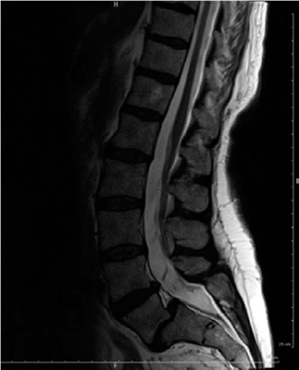

A 30-year-old male with chronic L5-S1 isthmic spondylolisthesis (Grade II) complains of persistent low back pain and bilateral S1 radiculopathy despite 9 months of conservative treatment. On examination, he has bilateral hamstring tightness and a positive straight leg raise test at 45 degrees. Which of the following imaging modalities is most crucial for evaluating potential nerve root compression and planning surgical decompression?

Explanation

While plain radiographs define the slip, and CT can better visualize bony stenosis, MRI is superior for evaluating soft tissue structures, including nerve roots, discs, and the spinal cord, and identifying nerve root compression by hypertrophic soft tissue, disc herniation, or foraminal stenosis, which is critical for surgical planning in patients with radiculopathy. EMG assesses nerve function but isn't an imaging modality for structural compression.